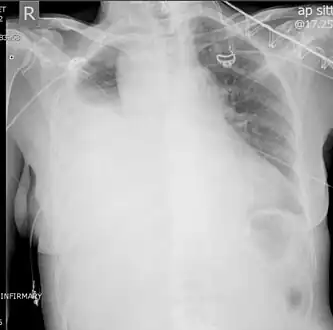

| Chest X-ray showing left sided hemothorax (arrowed) | |

A chest X-ray is the most common technique used to diagnosis a hemothorax.[23] X-rays should ideally be taken in an upright position (an erect chest X-ray), but may be performed with the person lying on their back (supine) if an erect chest X-ray is not feasible. On an erect chest X-ray, a hemothorax is suggested by blunting of the costophrenic angle or partial or complete opacification of the affected half of the thorax. On a supine film the blood tends to layer in the pleural space, but can be appreciated as a haziness of one half of the thorax relative to the other.[5] A small hemothorax may be missed on a chest X-ray as several hundred milliliters of blood can be hidden by the diaphragm and abdominal viscera on an erect film. Supine X-rays are even less sensitive and as much as one liter of blood can be missed on a supine film.[24]